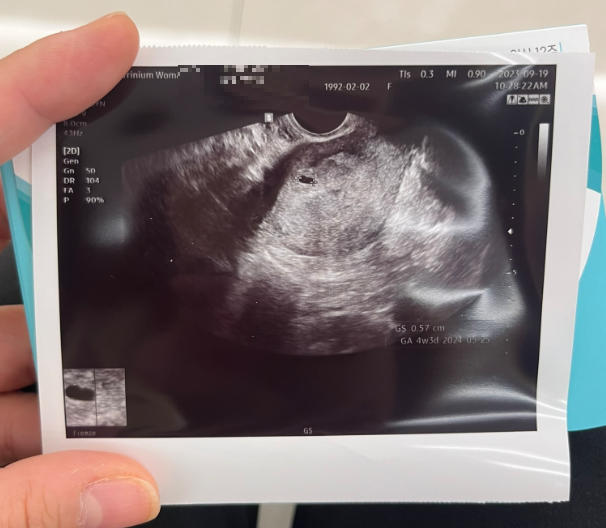

일단 집에서 가까운 '트리니움 여성 병원'으로 갔다.

와이프가 먹고싶어하는 떡볶이를 먹으며 초음파 사진을 건네받았다.

그리고 오늘 처음 알게 된것은 아이가 4주차라는것.